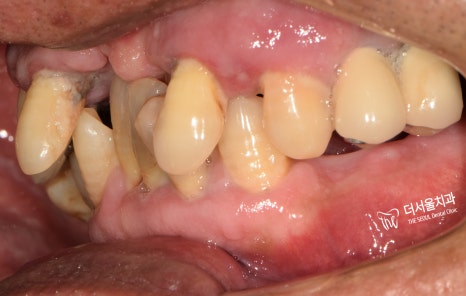

먼저 환자분 구내를 살펴보겠습니다.

상태가 너무도 좋지 않았습니다.

전체적으로 교합이 잘 이뤄지지 않고

윗니는 잇몸이 크게 부어있습니다.

게다가 많은 이가 흔들리고 있었구요.

오랜 기간에 걸쳐 치료를 받으셔야 되겠구나

라는 생각이 들었습니다.